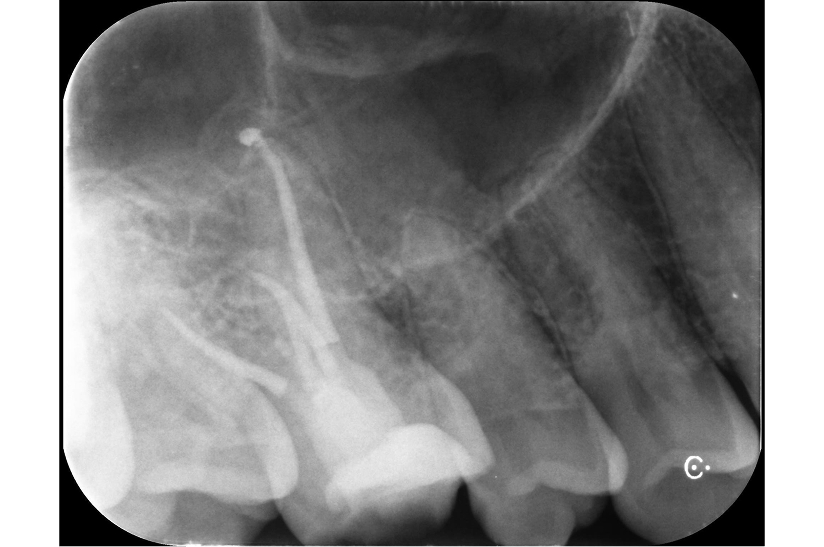

根尖性歯周炎の歯を

再根管治療によって歯を残した症例

タップで写真の拡大ができます。

Before

After

Under Treatment

主訴

抜歯が必要と言われた歯の精査を希望

診断

根尖性歯周炎(根尖吸収、ストリップパーフォレーションを伴う)

治療方針

重度の感染および根管内の損傷が認められる難症例であったが、 歯質の残存量および歯周組織の状態から保存可能と判断した。

歯根破折を疑う所見も認められなかったため、 患者の希望も踏まえ、保存的に再根管治療を行う方針とした。

治療内容

リトリートメント(大臼歯)、MTAセメントによる封鎖、レジンコア

治療期間

約1ヶ月

治療費用

220,000

結果

初診時には根管内に肉芽組織および排膿を認めたが、 感染コントロール後に炎症所見は消失した。

その後MTAセメントにて封鎖を行い、 術後症状は認めず、根尖病変は縮小傾向を示している。

治療の

リスク

根尖病変が完全に消失しない可能性

考察

複数回の根管治療既往があり、根管内は複雑な状態であったが、 適切な感染源の除去と封鎖により良好な経過が得られている。

難症例においては、保存の可否を適切に判断した上で、 精密な処置を行うことが重要である。